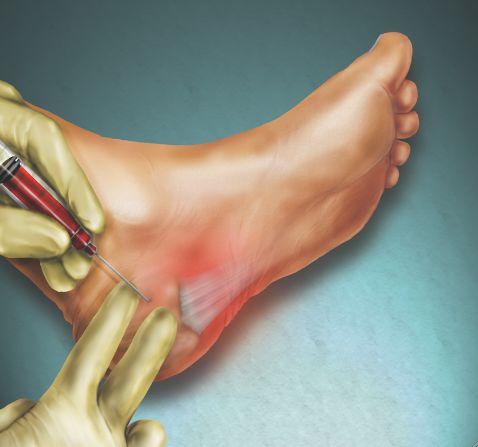

注射/封闭。将一种类固醇药物注射到疼痛区域可以暂时缓解疼痛。不建议多次注射,因为它们可以削弱你的足底筋膜,并可能导致其破裂。最近的疗法是在超声引导下注射富含血小板的血浆,在缓解疼痛的同时减轻组织破裂的风险。